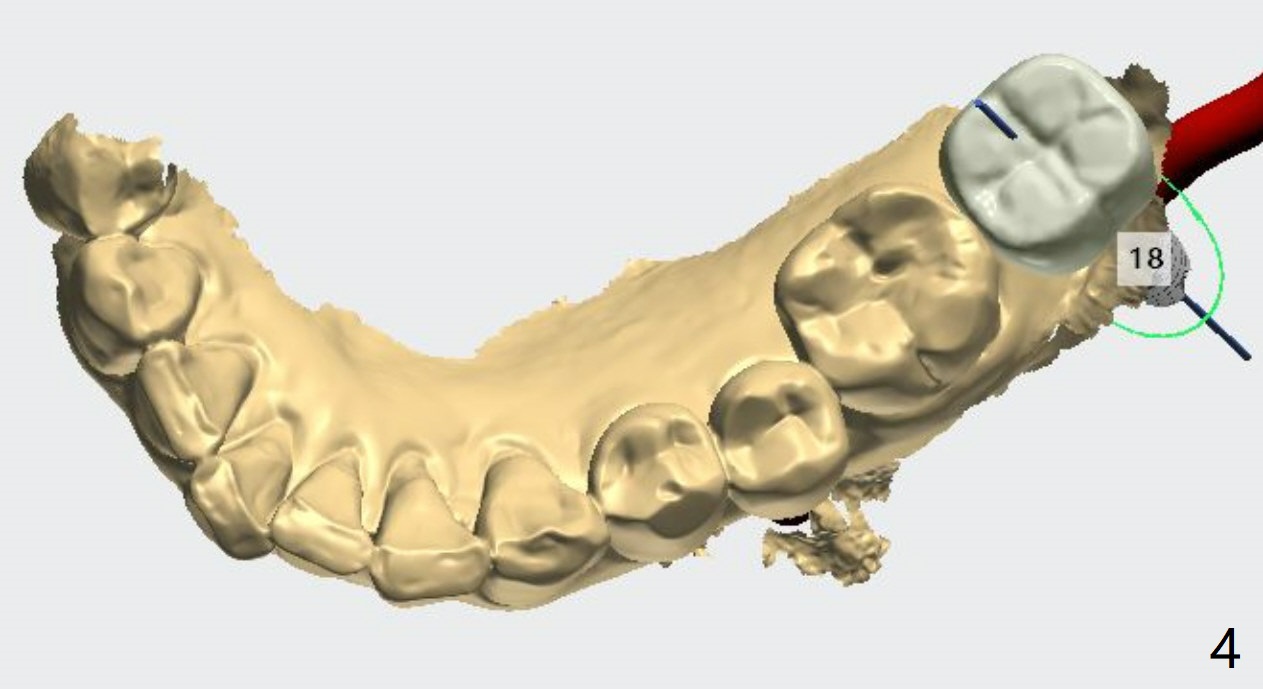

Narrow Fixture Bypasses Nerve